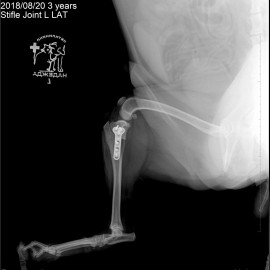

Наш пациент собака по кличке Артемон. Обратились с жалобами на остро развившуюся хромоту на заднюю левую лапу. После осмотра и рентгенологического исследования был поставлен диагноз - разрыв передней крестообразной связки левого коленного сустава. Была проведена операция- TPLO.

Снимки 3-4 после проведённой операции.